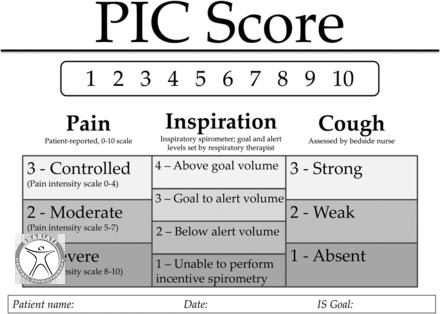

بهبود شکستگی دنده عموماً ۳ تا ۸ هفته به طول می انجامد برای تسریع درمان ورزشکار باید از فعالیت های شدید بپرهیزد و از اعمال فشار به دنده آسیب دیده جلوگیری کند باید ورزشکار را تشویق کرد که روزانه چندین نوبت نفس عمیق بکشد تا ظرفیت ریه ها کاهش نیابد.

ورزشکارانی که در رشته های پر برخورد فعالیت دارند و دنده بر اثر شکستگی جابجا شده یا در سمت شکسته درد قابل ملاحظه ای دارند باید در ادامه فصل مسابقات از جلیقه محافظ استفاده کنند. ورزشکاران رشته های بدون برخورد معمولا به محافظ و بریس نیاز ندارند مگر اینکه در ناحیه شکستگی درد داشته یا دچار مشکل تنفسی شود. ورزشکارانی که تحت درمان قرار گرفته و بهبود یافته اند باید تحت تمرینات آمادگی جسمانی قرار بگیرند تا ظرفیت های قلبی و تنفسی آنها پیش از بازگشت به بازی بهبود یابد.